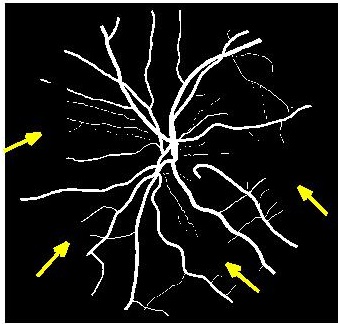

Figure 5 shows results of MA segmentation using the images generated by different super resolution methods. Figure 5 (a) shows the original full sized image with the regions having majority of the MAs outlined by a red square. Figure 5 (b) shows the cropped image region with yellow arrows identifying location of MAs. Figure 5 (c) shows manually drawn contours around the MAs. Figure 5 (d) shows the segmentation results obtained using the original HR images as part of the training and test set. The ground truth manual contours are shown in green while the segmentations obtained using the U-Net algorithm is shown in red. The performance on the HR images is an indication of the minimum error (or best possible segmentation performance). Figures 5 (e)-(h) show, respectively, the super resolved images obtained by , , and along with the super imposed segmentation results. It is quite obvious that the results obtained using are the best. It is interesting to note that the SR images obtained using and lead to blurred edges of the blood vessels and MAs, although in the case of the SR images are not blurred. The other two methods, and result in such poor quality images that the MAs are not even detected for this particular example.